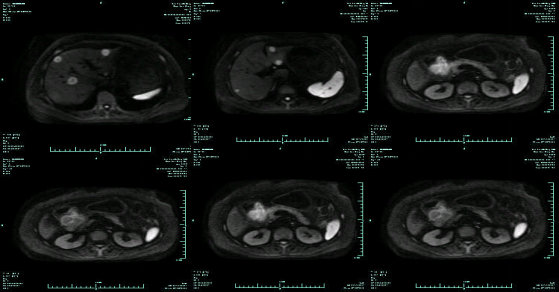

CT-T

CT-H1

MR-H1

影像学检查结果评估:cPD。